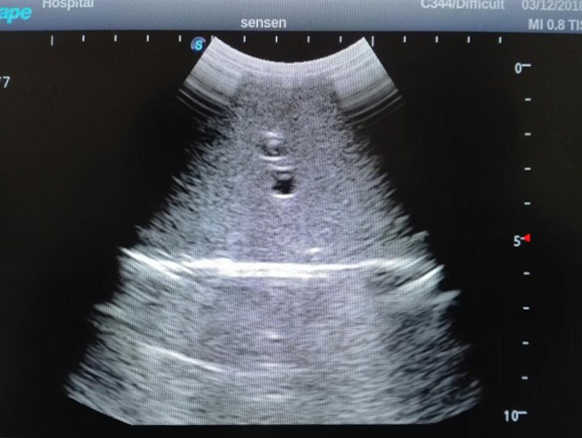

Abdominal Ultrasound Phantom

Model TYE1569

Outline

This product is a true-to-life male torso designed for abdominal ultrasound training. It offers you an effective solution for preparing learners for routine abdomen checkup including percussion, various puncture under ultrasound guidance and ultrasound image reading. The realism of the product and the skillset specific to abdominal examination techniques will bring learners competence and confidence.

2)  High quality ultrasound image with clear structures like gallbladder, liver, intestines, arteries and veins etc.